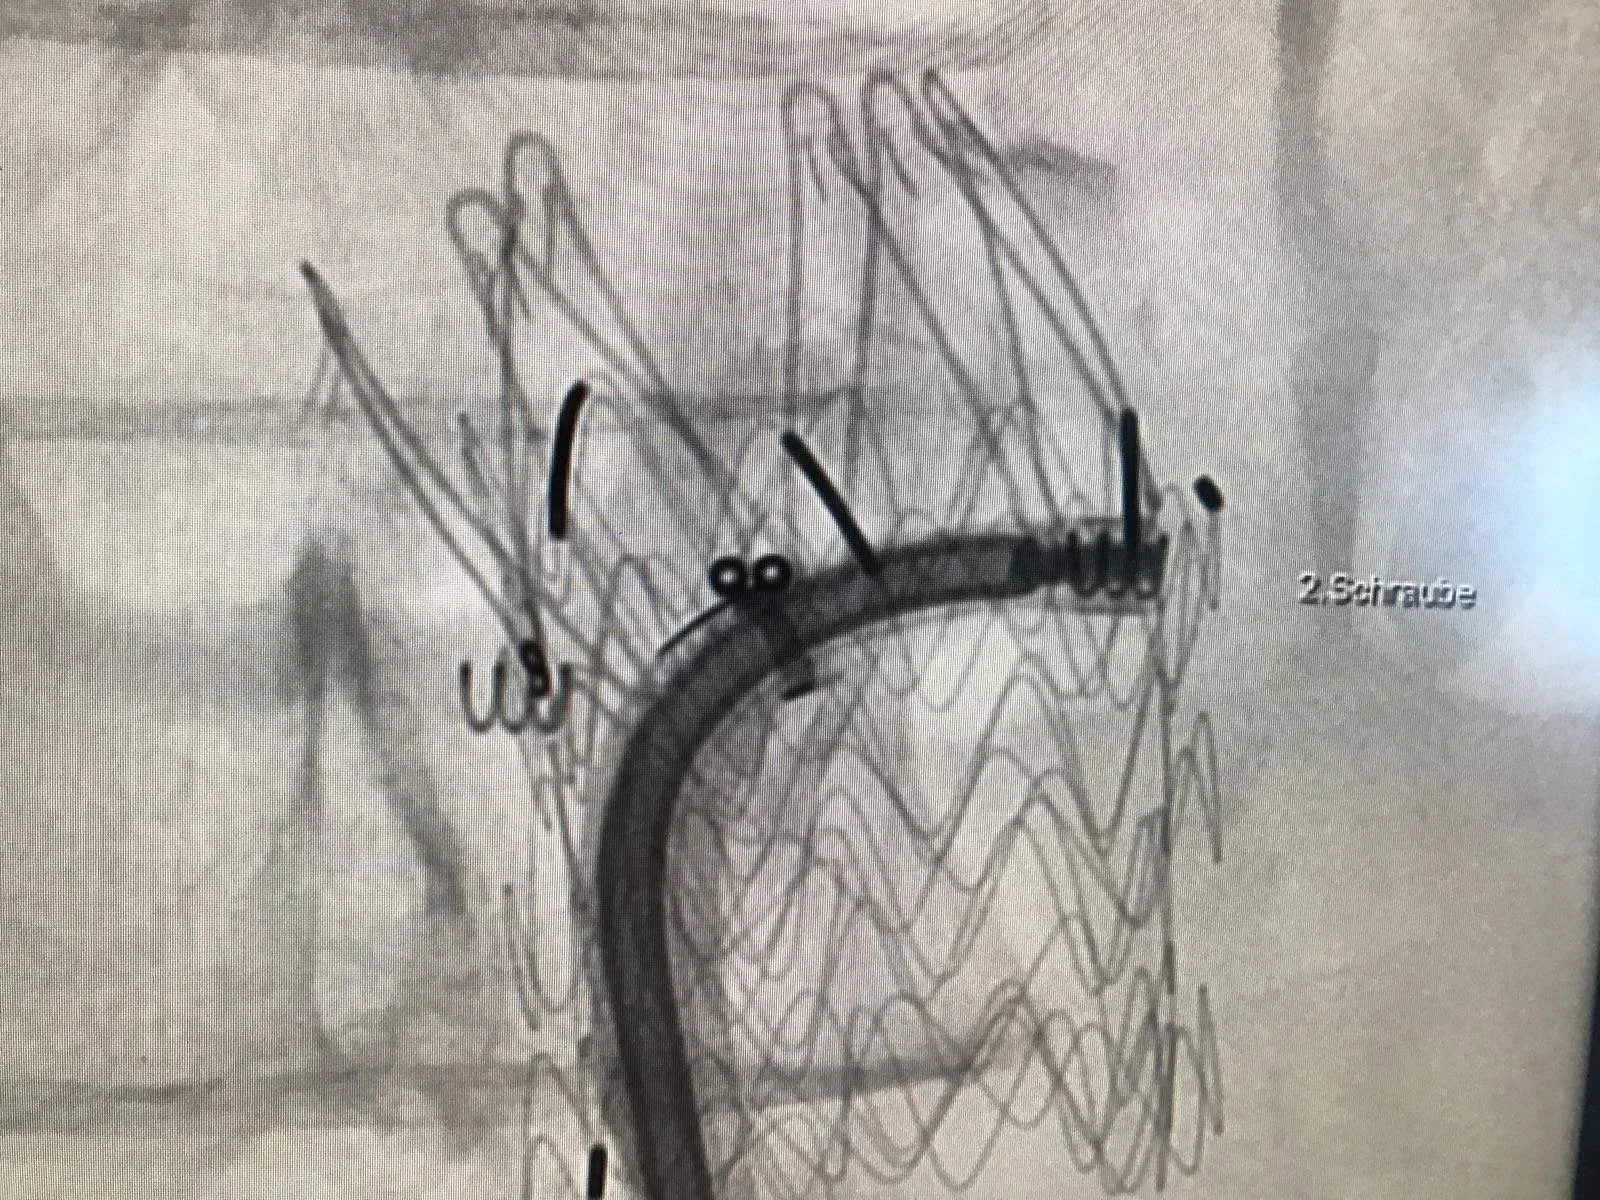

• Minimal-invasive Eingriffe bei der Aorta (EVAR, FEVAR, TEVAR)

Ich bin ein anerkannter Facharzt für Herz- und thorakale Gefässchirurgie sowie Chirurgie mit Schwerpunkt Aortenchirurgie & komplexer Gefässchirurgie. Mit umfassender internationaler Erfahrung, unter anderem als Consultant Vascular Surgeon am Guy’s and St. Thomas’ NHS Trust in London und als Chef de Clinique an der CHU Bichat-Claude Bernard in Paris, biete ich modernste gefässchirurgische Behandlungen auf höchstem Niveau. Meine Expertise umfasst minimal-invasive endovaskuläre Verfahren, komplexe Aortenchirurgie, Karotis-Chirurgie sowie venöse Eingriffe. Ich bin Mitglied der FMH und verfügt über Zusatzausbildungen wie Phlebologie (USGG) und Endovenöse thermische Ablation.

• Leitender Arzt (Stv.) Gefässchirurgie, Leiter endovaskuläre Gefässchirurgie, Kantonsspital Baden, CH